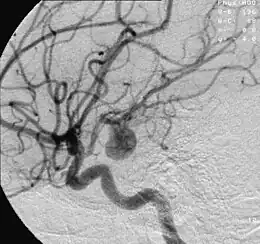

Angiographie d'un anévrisme sur une artère cérébrale.